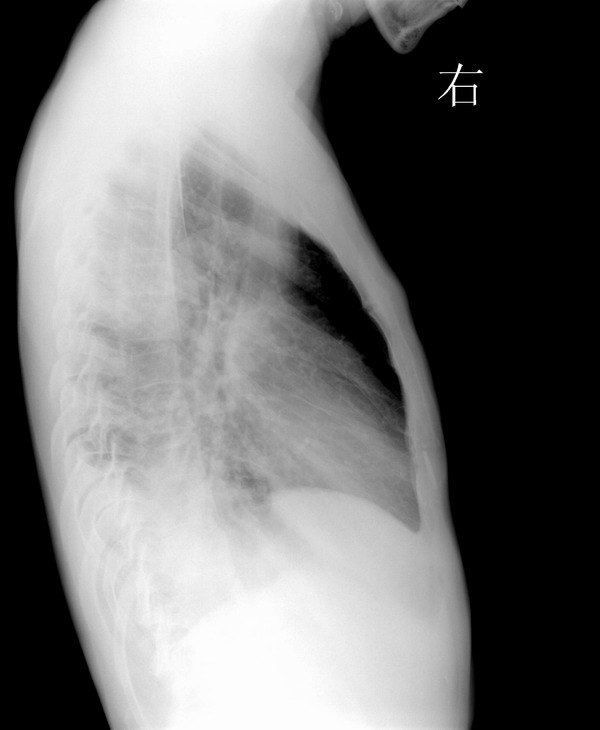

男,34y,发热寒颤月余,脓痰!

右下肺沿支气管的小结结影,还发现粘连性改变,侧位可见后肋隔角消失,因此考虑:支气管肺炎,脓旬,包裹性积液

右下肺沿支气管的小结结影,还发现粘连性改变,侧位可见后肋隔角消失,因此考虑:支气管肺炎,脓胸,包裹性积液

颈肋.右肺下叶后基底段及左肺下叶背段炎变伴右侧胸腔包裹性积液

右下肺炎,右侧胸膜肥厚,右侧胸腔积液,双侧颈肋.

右肺下叶肺脓肿并胸腔积液

右肺下叶肺脓肿并胸腔积液,胸膜粘连.左肺炎症.颈肋.

1 双侧颈肋.  2右下肺炎,3左上叶前段节段性肺炎4右侧叶间积液?

右下肺炎,包裹性积液

右下肺炎症,拌肺底积液